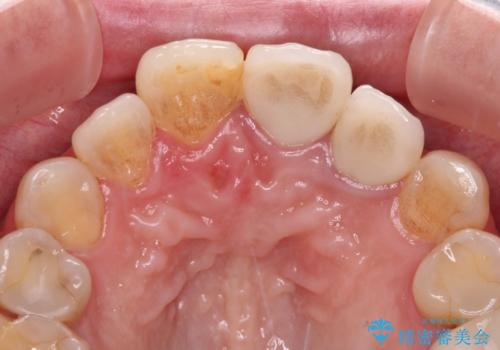

仮歯を装着した時点で、口元が気にならなくなったので、患者様が感じていた違和感の原因は変色した前から2番目の歯であったと思われます。

形態や色彩が左右対称となるように仕上がり、患者様には大変満足していただきました。